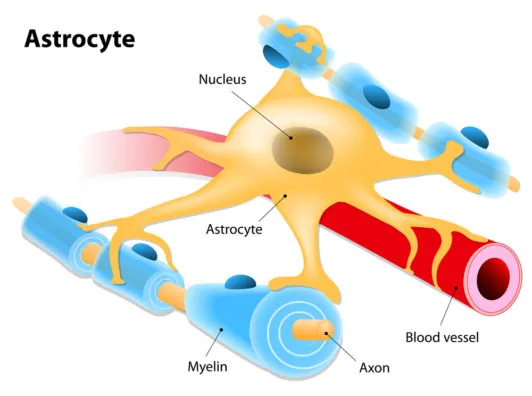

The thymus is a specialized organ that produces the majority of immune T cells, and as we age, it shrinks in size and ability to produce these cells. This process is called involution.

Some of the most critical cancer-fighting immune cells are the T cells produced by the thymus. As aging causes the organ to shrink and turn into fat, the output of T cells falls to critically low levels and opens us up to cancer and other diseases.

In your paper, you note that the body does continue to create T cells even when the thymus has involuted to the point that it is effectively useless. T cells are produced elsewhere in the body, particularly via peripheral clonal expansion. However, despite the level of T cells remaining relatively constant even in old age due to clonal expansion, these T cells do not appear to do a very good job at keeping cancer at bay; why is this?

That’s right, although I’m not sure the thymus is ever effectively useless, but it does get very small. T-cells develop from hematopoietic stem cells; they first develop a “random” T-cell receptor then pass through a selection process in the thymus, ensuring that they are not self-reactive, then they replicate (clonal expansion). With age, the rate of T-cell production goes down, but the rate of clonal expansion goes up, resulting in an approximately constant total number of T-cells. This finding that T-cell production is inversely proportional to disease risk suggests that this clonal expansion does not increase the effectiveness of T-cells. I think testing that directly would make a great experiment.

There was an interesting paper recently that showed that the effectiveness of T-cells depends linearly on co-stimulatory factors. Perhaps whatever mechanism is behind that may explain both phenomena.